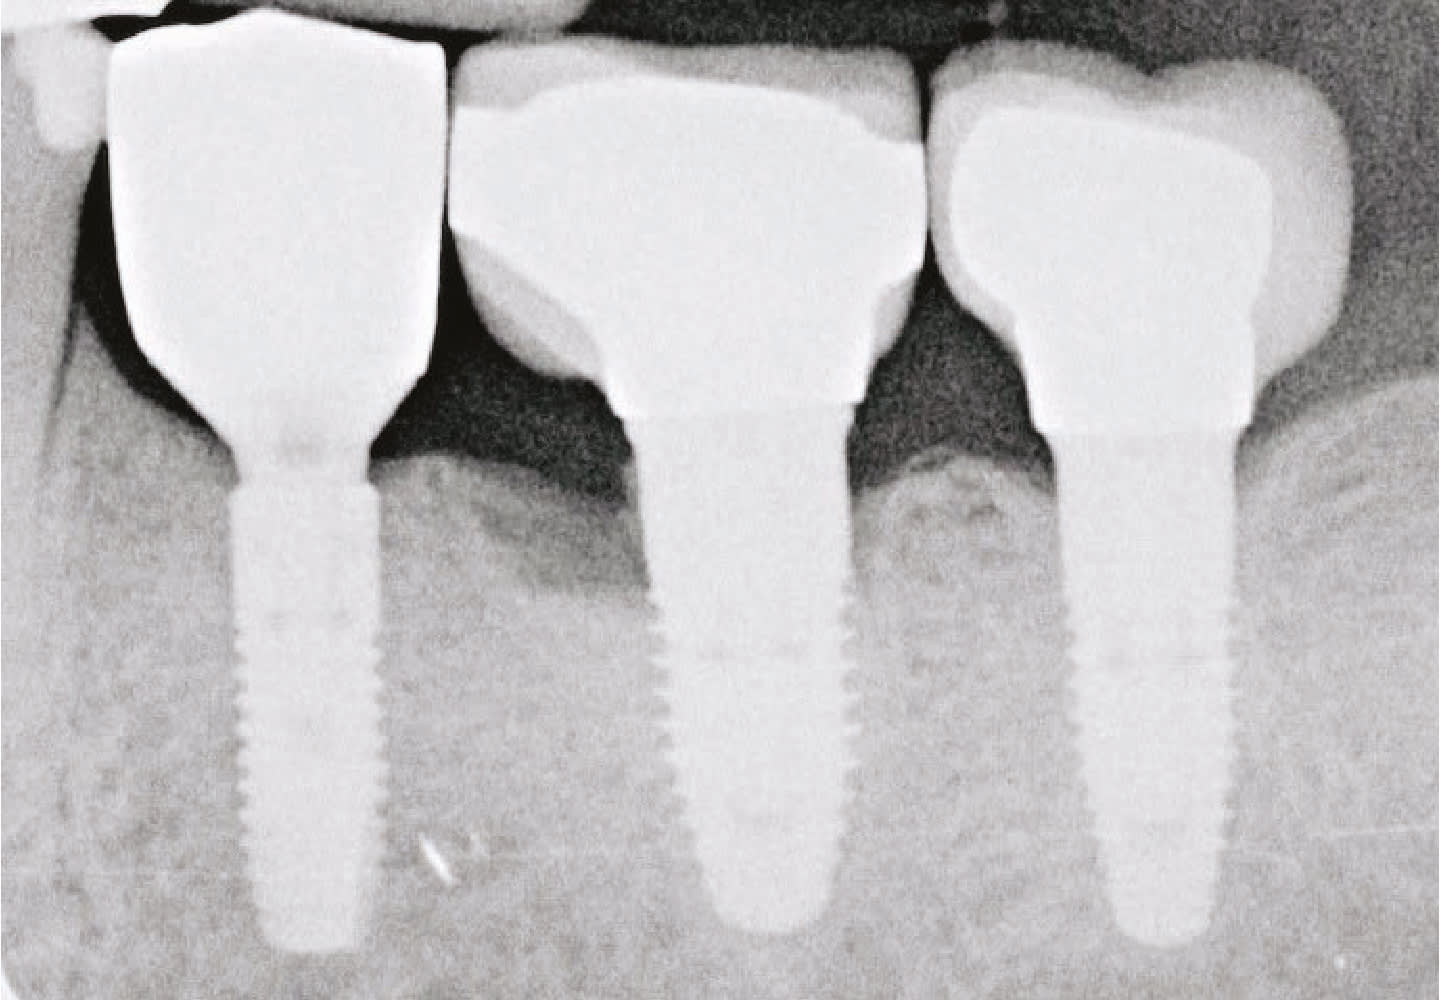

Dr. Wong also uses the PerioLase MVP-7 for the LAPIP™ protocol to treat peri-implantitis and save ailing and failing implants. In addition, the laser’s exclusive BLAST™ protocol for peri-implantitis and osseointegration is designed for long-term implant success.

- The laser is also used to perform the LAPIP™ protocol for the treatment of peri-implantitis, providing a minimally invasive option for addressing infection around dental implants.